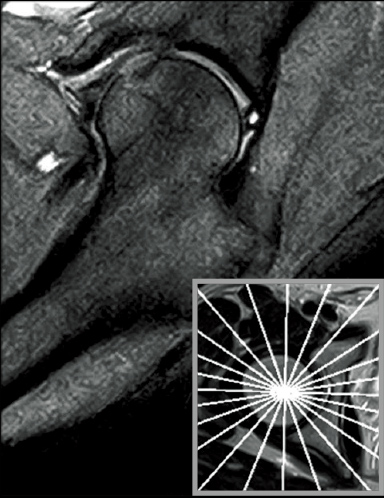

T2*WI RadialStack